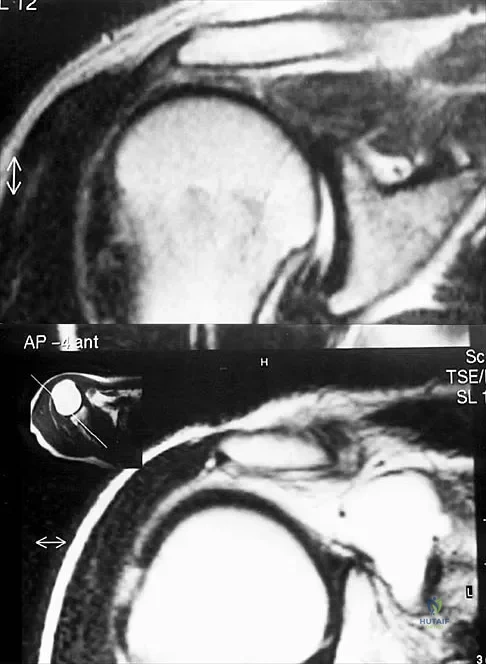

Figures 49a and 49b show MRI scans of the shoulder. What is the most likely diagnosis?

Explanation

A 25-year-old tennis player has shoulder pain and weakness to external rotation. MRI scans are shown in Figures 16a and 16b. What is the most likely cause of his weakness?

Figures 39a and 39b show the MRI scans of a 25-year-old man with right shoulder pain. Figure 39c shows the arthroscopic view from a posterior portal in the beach chair position. What is the most likely diagnosis?

Explanation